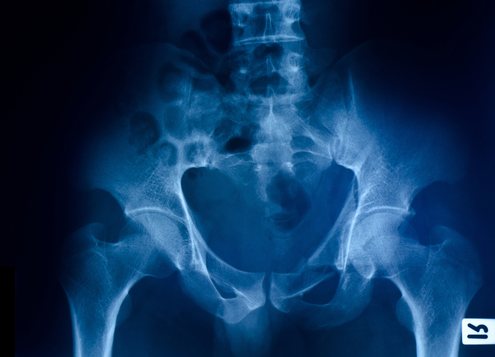

Teleradiology – the most mature area of telehealth.

So mature in fact that in the world of radiology, people consider it as part of the mainstream.

photo: radiology/shutterstock